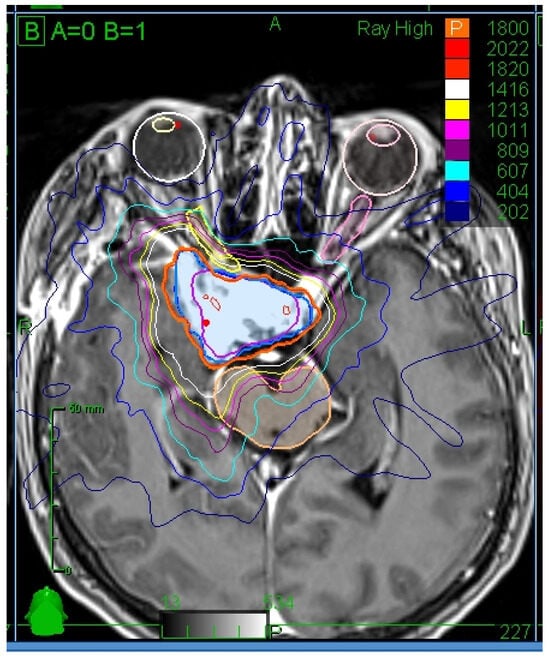

2.2. Radiotherapy Treatment Planning and Delivery